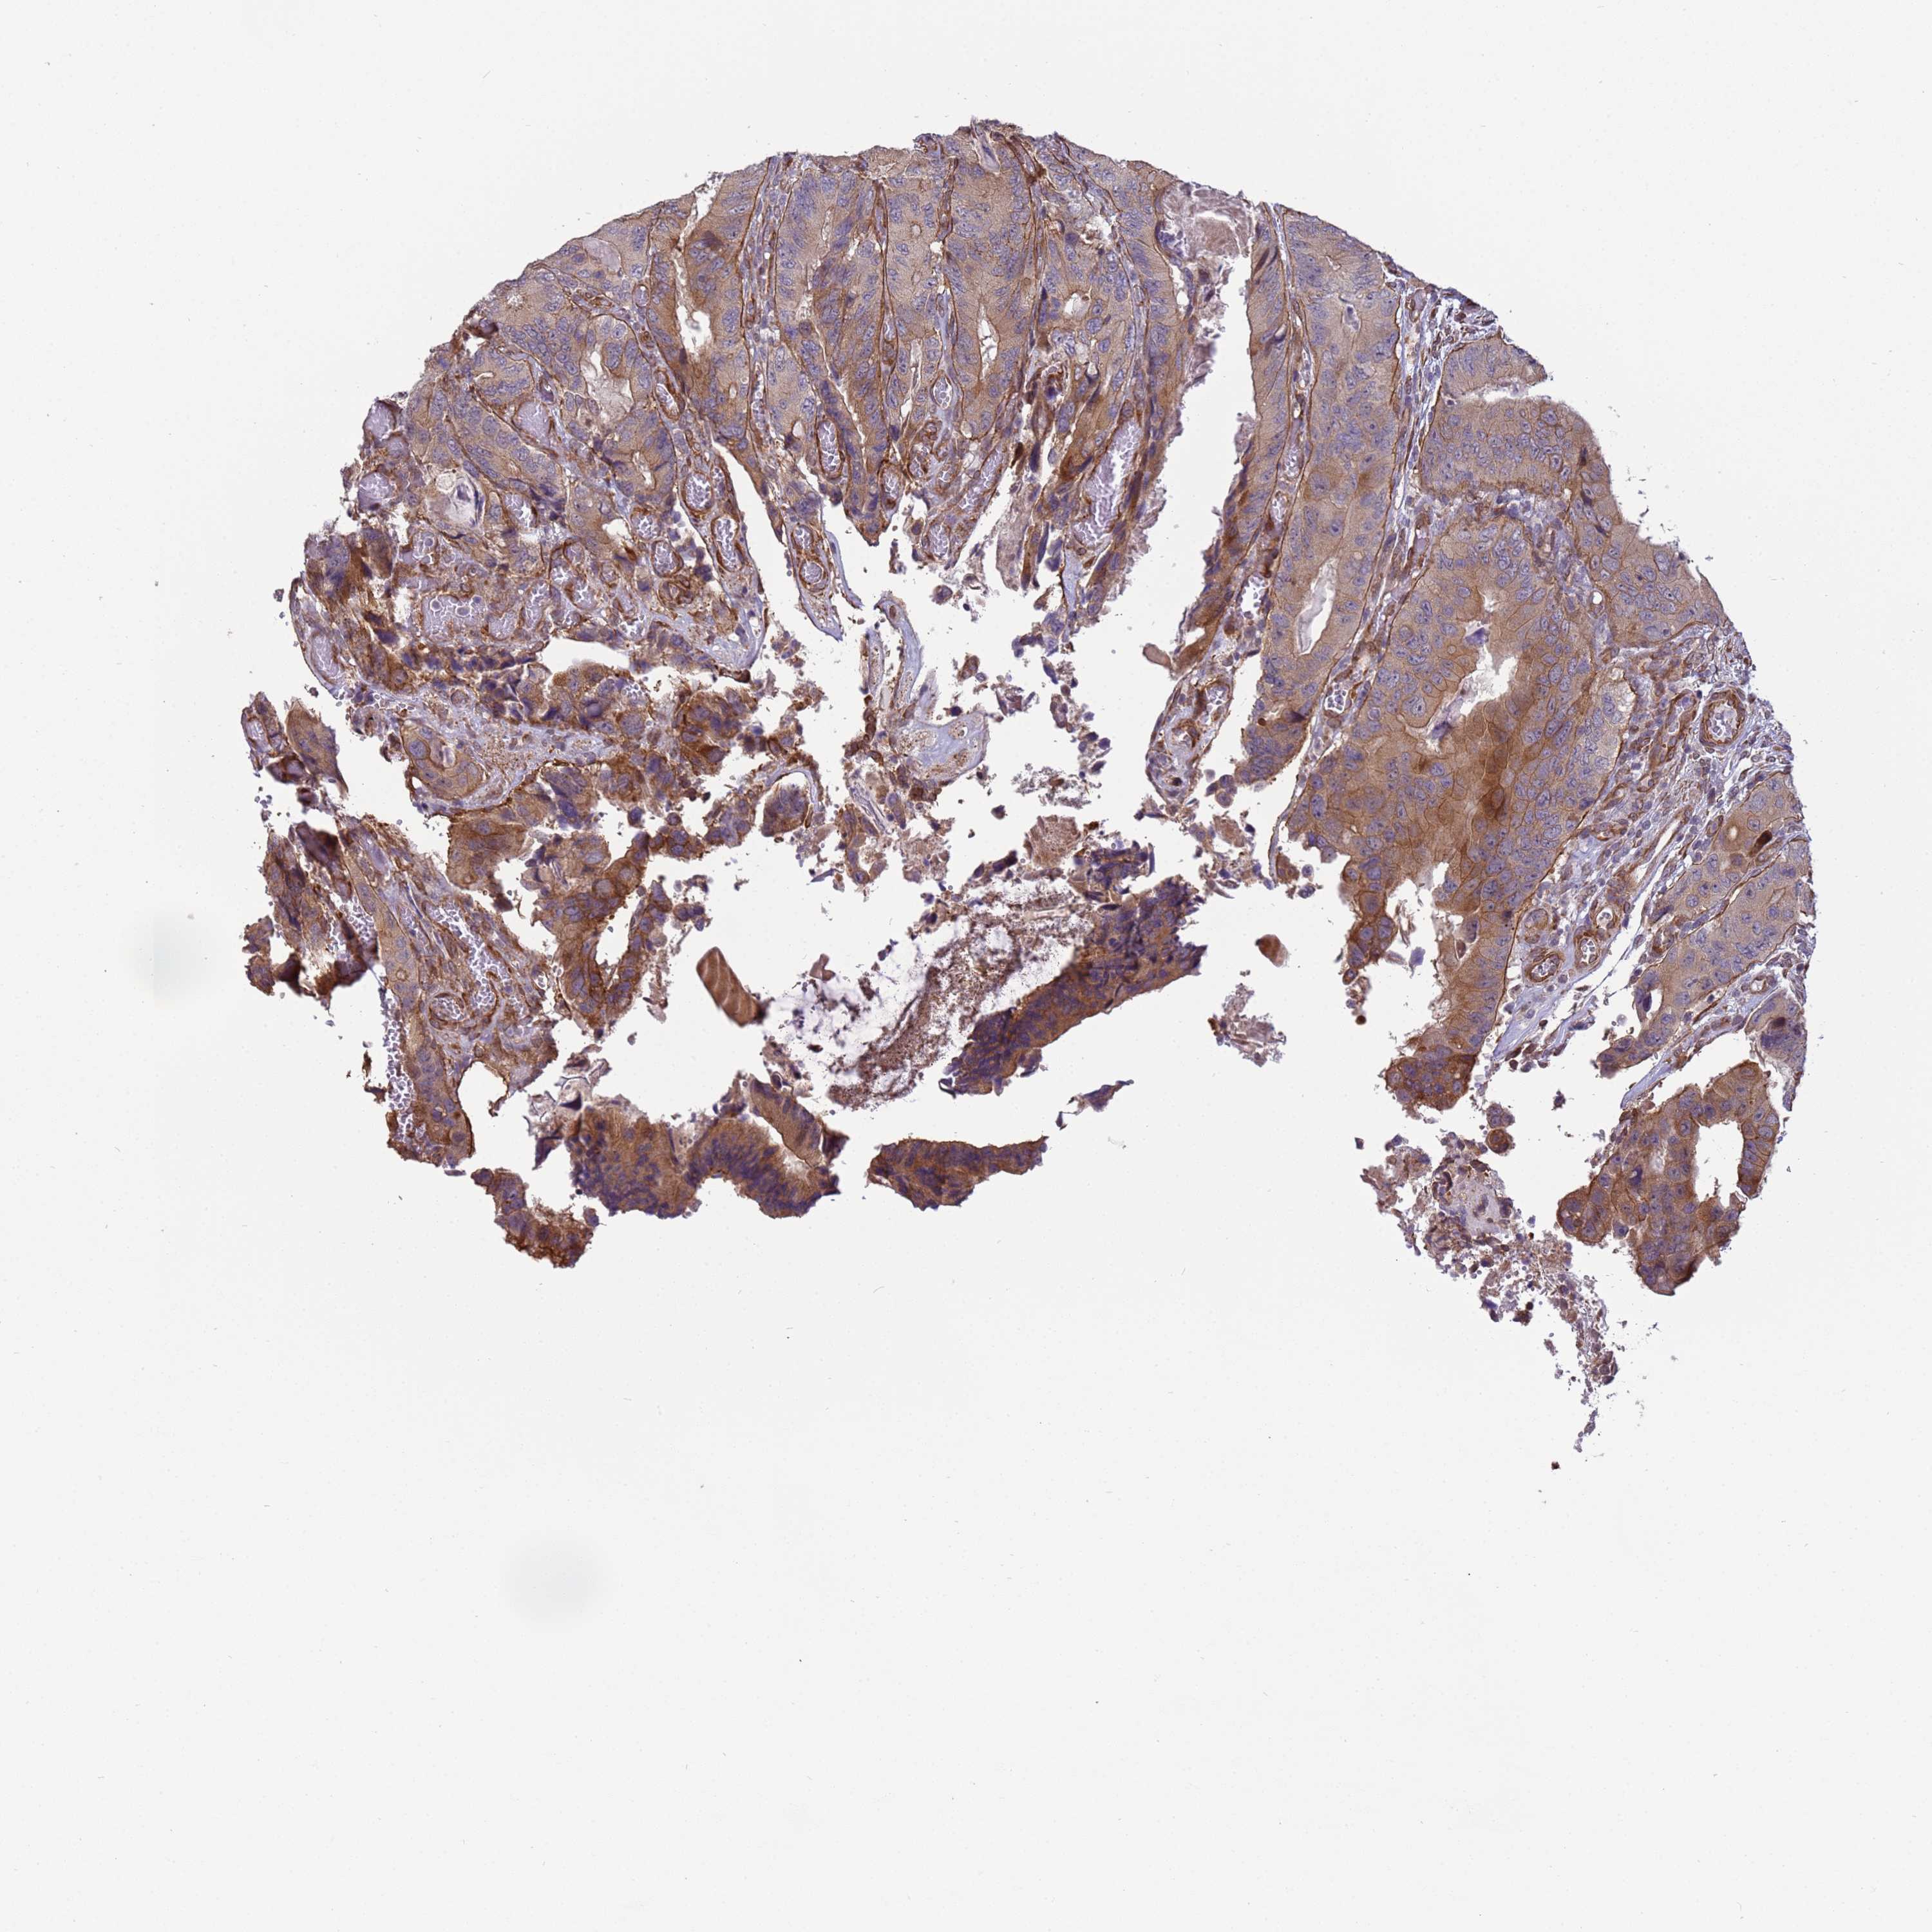

CANCER COLORECTAL CANCER Show tissue menu

Colorectal cancer

Human cancer

Colon adenocarcinoma